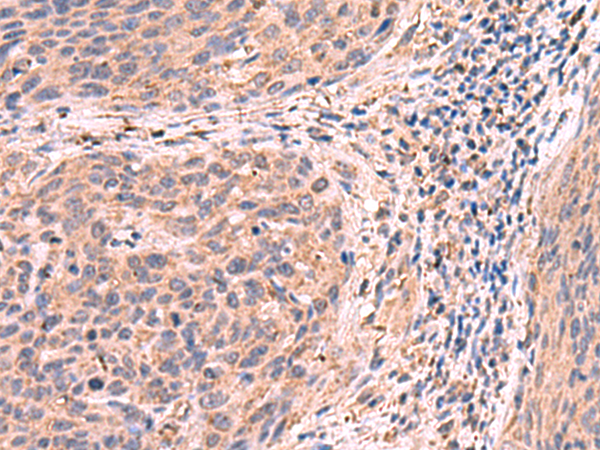

分类: 科研抗体货号: P10118别名: QA1; HLA-6.2应用: IHC反应种属: Human